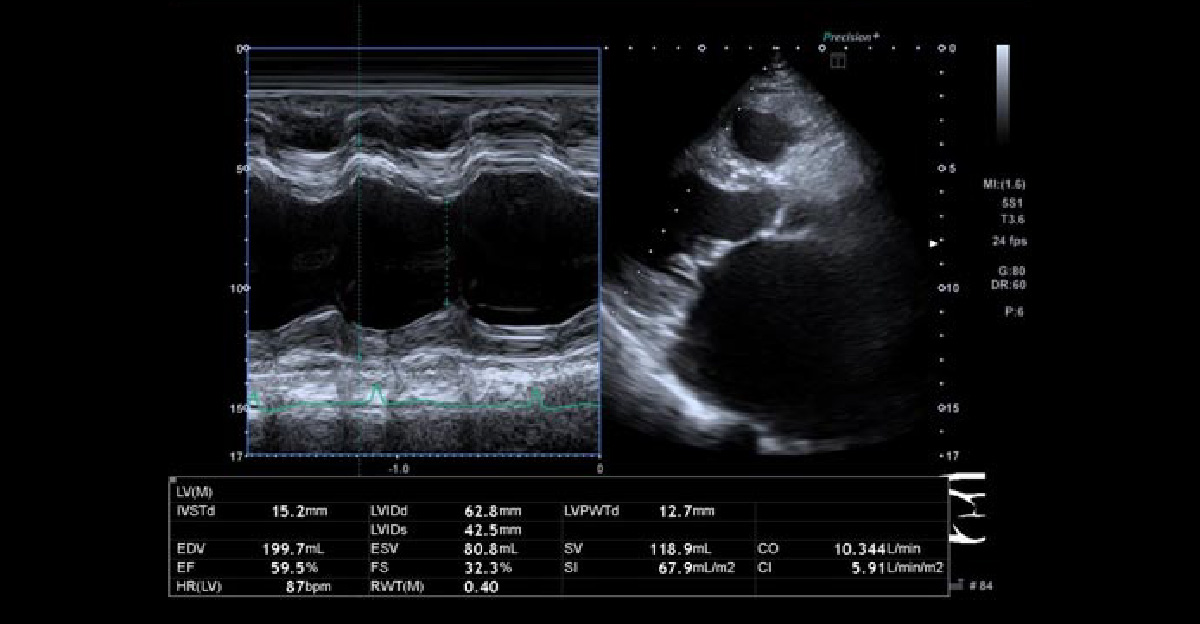

心臓の状心不全は、機能低下で大きく2パターンに分類されます。

1. 収縮力↓(+拡張能↓) → 動きが悪いか?

2. 拡張能↓ → 硬いか?

心不全の結果として、心臓の壁が厚くなるか?心臓そのものが大きくなるか?となります。心臓エコーによる評価が重要です。

拡張能を評価する5項目

1. 左室流入血流波形 E. A. E/A

2. 僧帽弁輪運動速度 e′

3. 平均E/e′

4. 左房容積係数

5. 最大三尖弁逆流速度